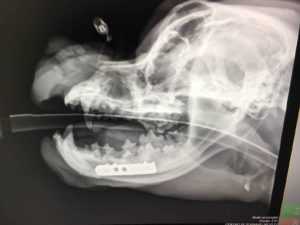

Los últimos casos de Koncientizando son Mojoe y Luna Azul, su rescate fue el 22 de mayo pasado. «Mojoe estaba hecho pedazos» cuenta Anne Guzmán, presidenta de Koncientizando. El reporte cuenta que el animal cayó de unos 20 metros de alto. Cuando fue rescatado tenía un severo golpe en los pulmones, fractura en mandíbula y en una pata trasera; nadie pensó que sobreviviría.

A Luna y Mojoe les realizaron estudios de sangre, radiografías y tomografías en el Centro Veterinario México. Luna recibió lavados quirúrgicos en el hueso hasta que pudieron colocar un estabilizador en su pata. Mojoe estuvo en quirófano cuatro horas para reconstruir su pata y mandíbula. 15 personas de medicina interna, ortopedia, hospitalización, terapia intensiva y guardia participaron en la recuperación médica que todavía continúa.

Aún cuando el Centro Veterinario es aliado de Koncientizando, muchos de los gastos tienen que pagarse. Las complejas cirugías de Mojoe, sus medicamentos y hospitalización alcanzaron una cuenta que ronda los 50 mil pesos; con Luna el gasto fue cercano a 35 mil.